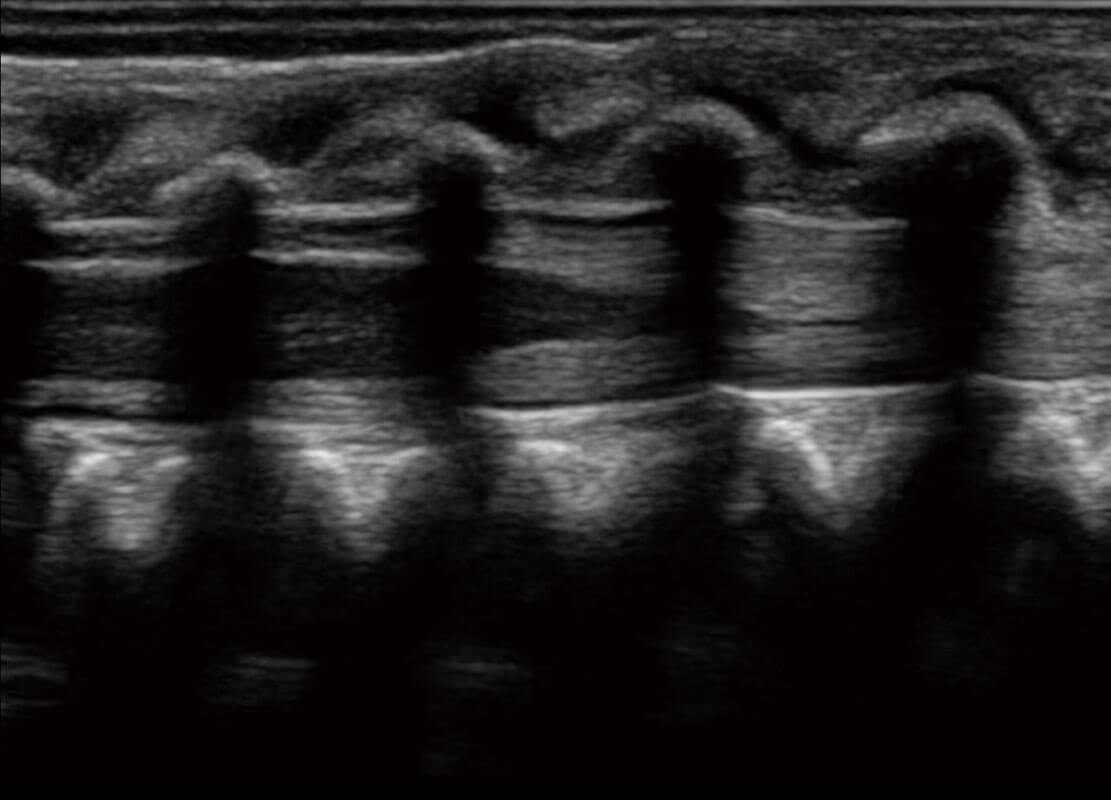

P60搭載寬頻帶線(xiàn)陣探頭、寬景成像、彈性成像技術(shù),為您提供乳腺應(yīng)用方案。P60支持高頻相控陣探頭、線(xiàn)陣探頭、腹部高頻探頭、腹部微凸探頭等,豐富的探頭群搭載敏感的彩色血流成像,適用于新生兒多種臟器檢測(cè)要求,滿(mǎn)足新生兒篩查需求。

新生兒心臟